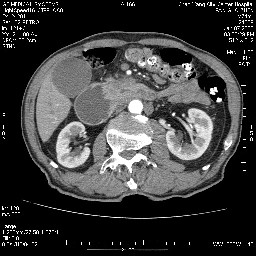

女,74岁,呕吐10余日

壶腹部的占位性病变,考虑为十二指肠癌并梗阻,但脾内多发性低密度区为转移吗?

还有胃、脾之间可见有侧支循环建立。左肾盂积水。

十二指肠水平段腔内占位伴梗阻,中等度较为均匀的强化,洗脱慢,区域淋巴结显示增多,符合腺癌表现。下腔静脉变异。

十二指肠降段扩张,水平段狭窄成鼠尾状,肠壁明显增厚,胰腺勾突增大成不均匀强化,其内可见低密度区,胆囊增大,1十二指肠水平段腺癌侵犯胰腺勾突可能大,2胰腺癌侵犯十二指肠(只有胆囊增大没有肝内外胆管扩张不好解释)代除外.

十二指肠降段扩张,水平段狭窄成鼠尾状,肠壁明显增厚,胰腺勾突增大成不均匀强化,其内可见低密度区,胆囊增大,1十二指肠水平段腺癌侵犯胰腺勾突可能大,2胰腺癌侵犯十二指肠 。

今日手术结果:胰腺钩突癌侵犯十二直肠,腹腔淋巴结转移.